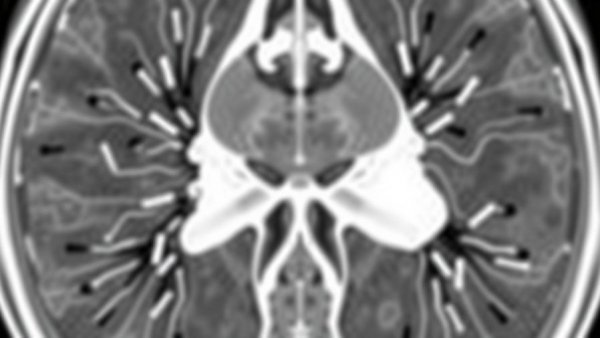

Magnetic Resonance Imaging (MRI) is not new to the medical field. However, its integration into prostate biopsies is revolutionary. MRIs are known for their ability to provide detailed images of soft tissues, making them an ideal tool for identifying abnormalities in the prostate. The new technique involves combining MRI imaging with biopsy procedures, allowing physicians to target suspicious lesions more precisely. This not only enhances accuracy but also reduces the need for repeat biopsies, which can be both invasive and emotionally taxing for patients.